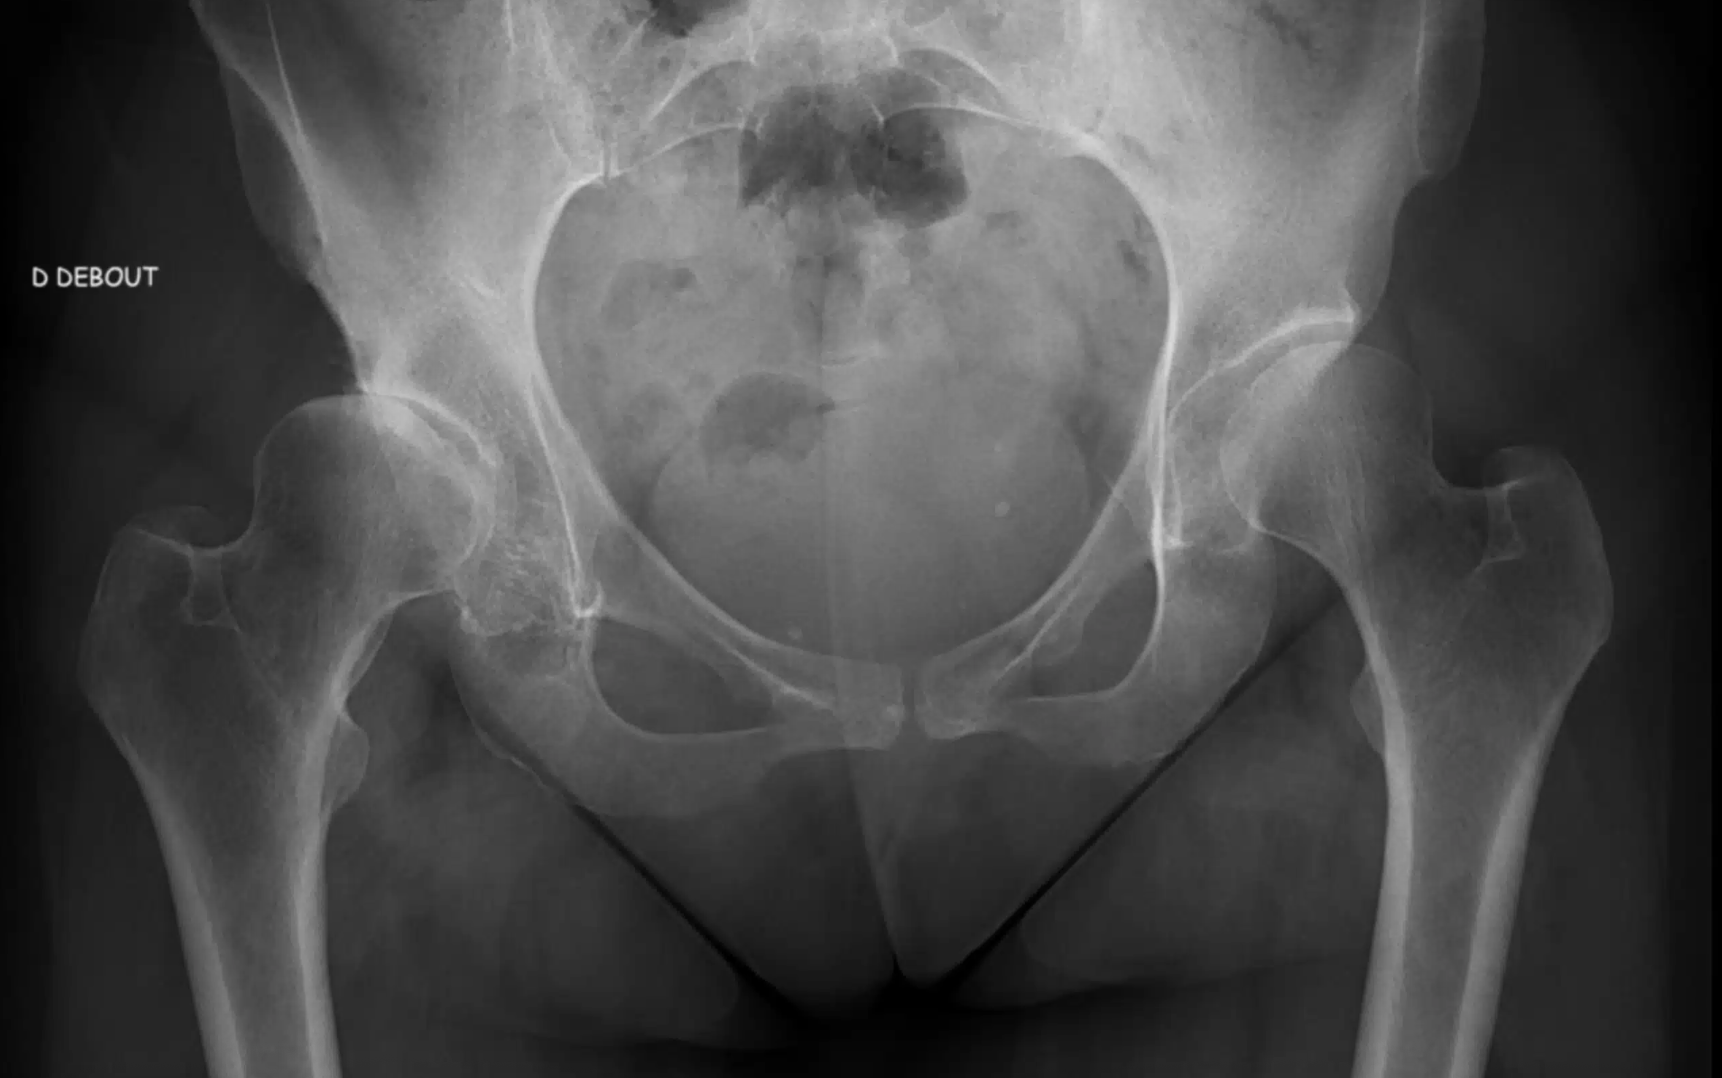

Chirurgie de la Hanche

Principalement indiquée pour traiter l’arthrose, réduire les douleurs articulaires et améliorer la mobilité, la chirurgie de la hanche est la principale spécialité exercée par le Dr Guilhem à l’Hôpital Privé Saint Roch à Toulon traite les pathologies orthopédiques, à travers de chirurgie programmée exclusive du membre inférieur, en particulier la chirurgie de l’arthrose (gonarthrose et coxarthrose).

Prothèse totale de hanche (PTH) par voie antérieure, reprise de prothèse de hanche, sont autant d’opérations programmées que les chirurgiens de l’Hôpital privé St Roch à Hyères peuvent proposer à leurs patients.

Ayant pour finalité de remplacer l’articulation très abîmée par l'arthrose par une articulation en matériel synthétique, c’est une indication non urgente qui oriente le patient vers le praticien de l’hôpital St Roch de Toulon, avec pour volonté principale d'améliorer le confort

Prenez rendez-vous dès maintenant avec le Docteur Kevin Guilhem, chirurgien orthopédique spécialisé du genou et de la hanche, de la chirurgie de l’arthrose et du sport, qui au cours d’une première consultation, sera à même de faire un premier état des lieux de votre état de santé et des pathologies qui vous touchent, et qui confirmera ou non la nécessité de mettre en place une prothèse de hanche ou de genou après la réalisation d’un interrogatoire, d’un examen clinique et après étude de votre bilan radiologique.